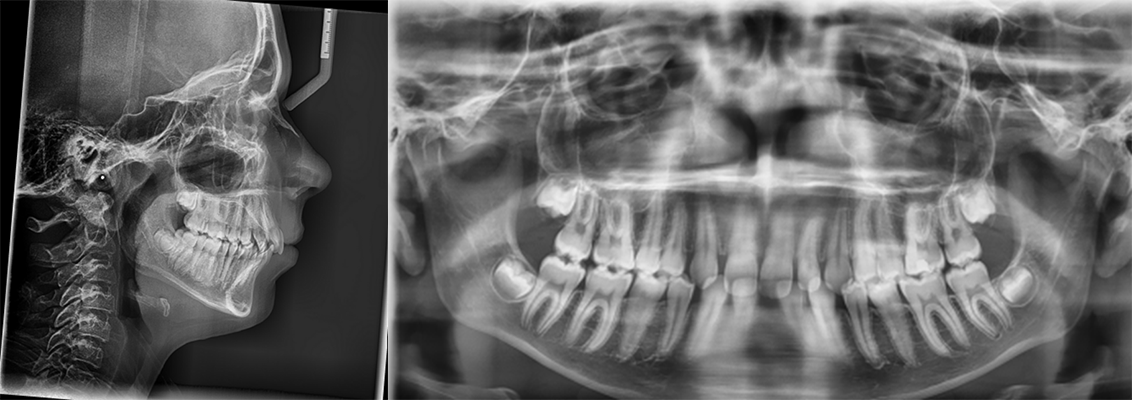

Age: 12 years

Main complaint: Aesthetic concerns and functional difficulties

Skeletal Class II due to mandibular retrognathia, proclination of maxillary incisors, narrow arch creating a V-shaped arch, agenesis of 12, 31, 41, hyperdivergent facial pattern, moderate deep bite (2 mm), increased overjet (9 mm), asymmetric canine and molar Class II due to mandibular deviation to the left, maxillary midline deviation related to agenesis of 12, distal rotation of 35 and 45, and pronounced lower curve of Spee.

Labial incompetence, mouth breathing, tongue dysfunction